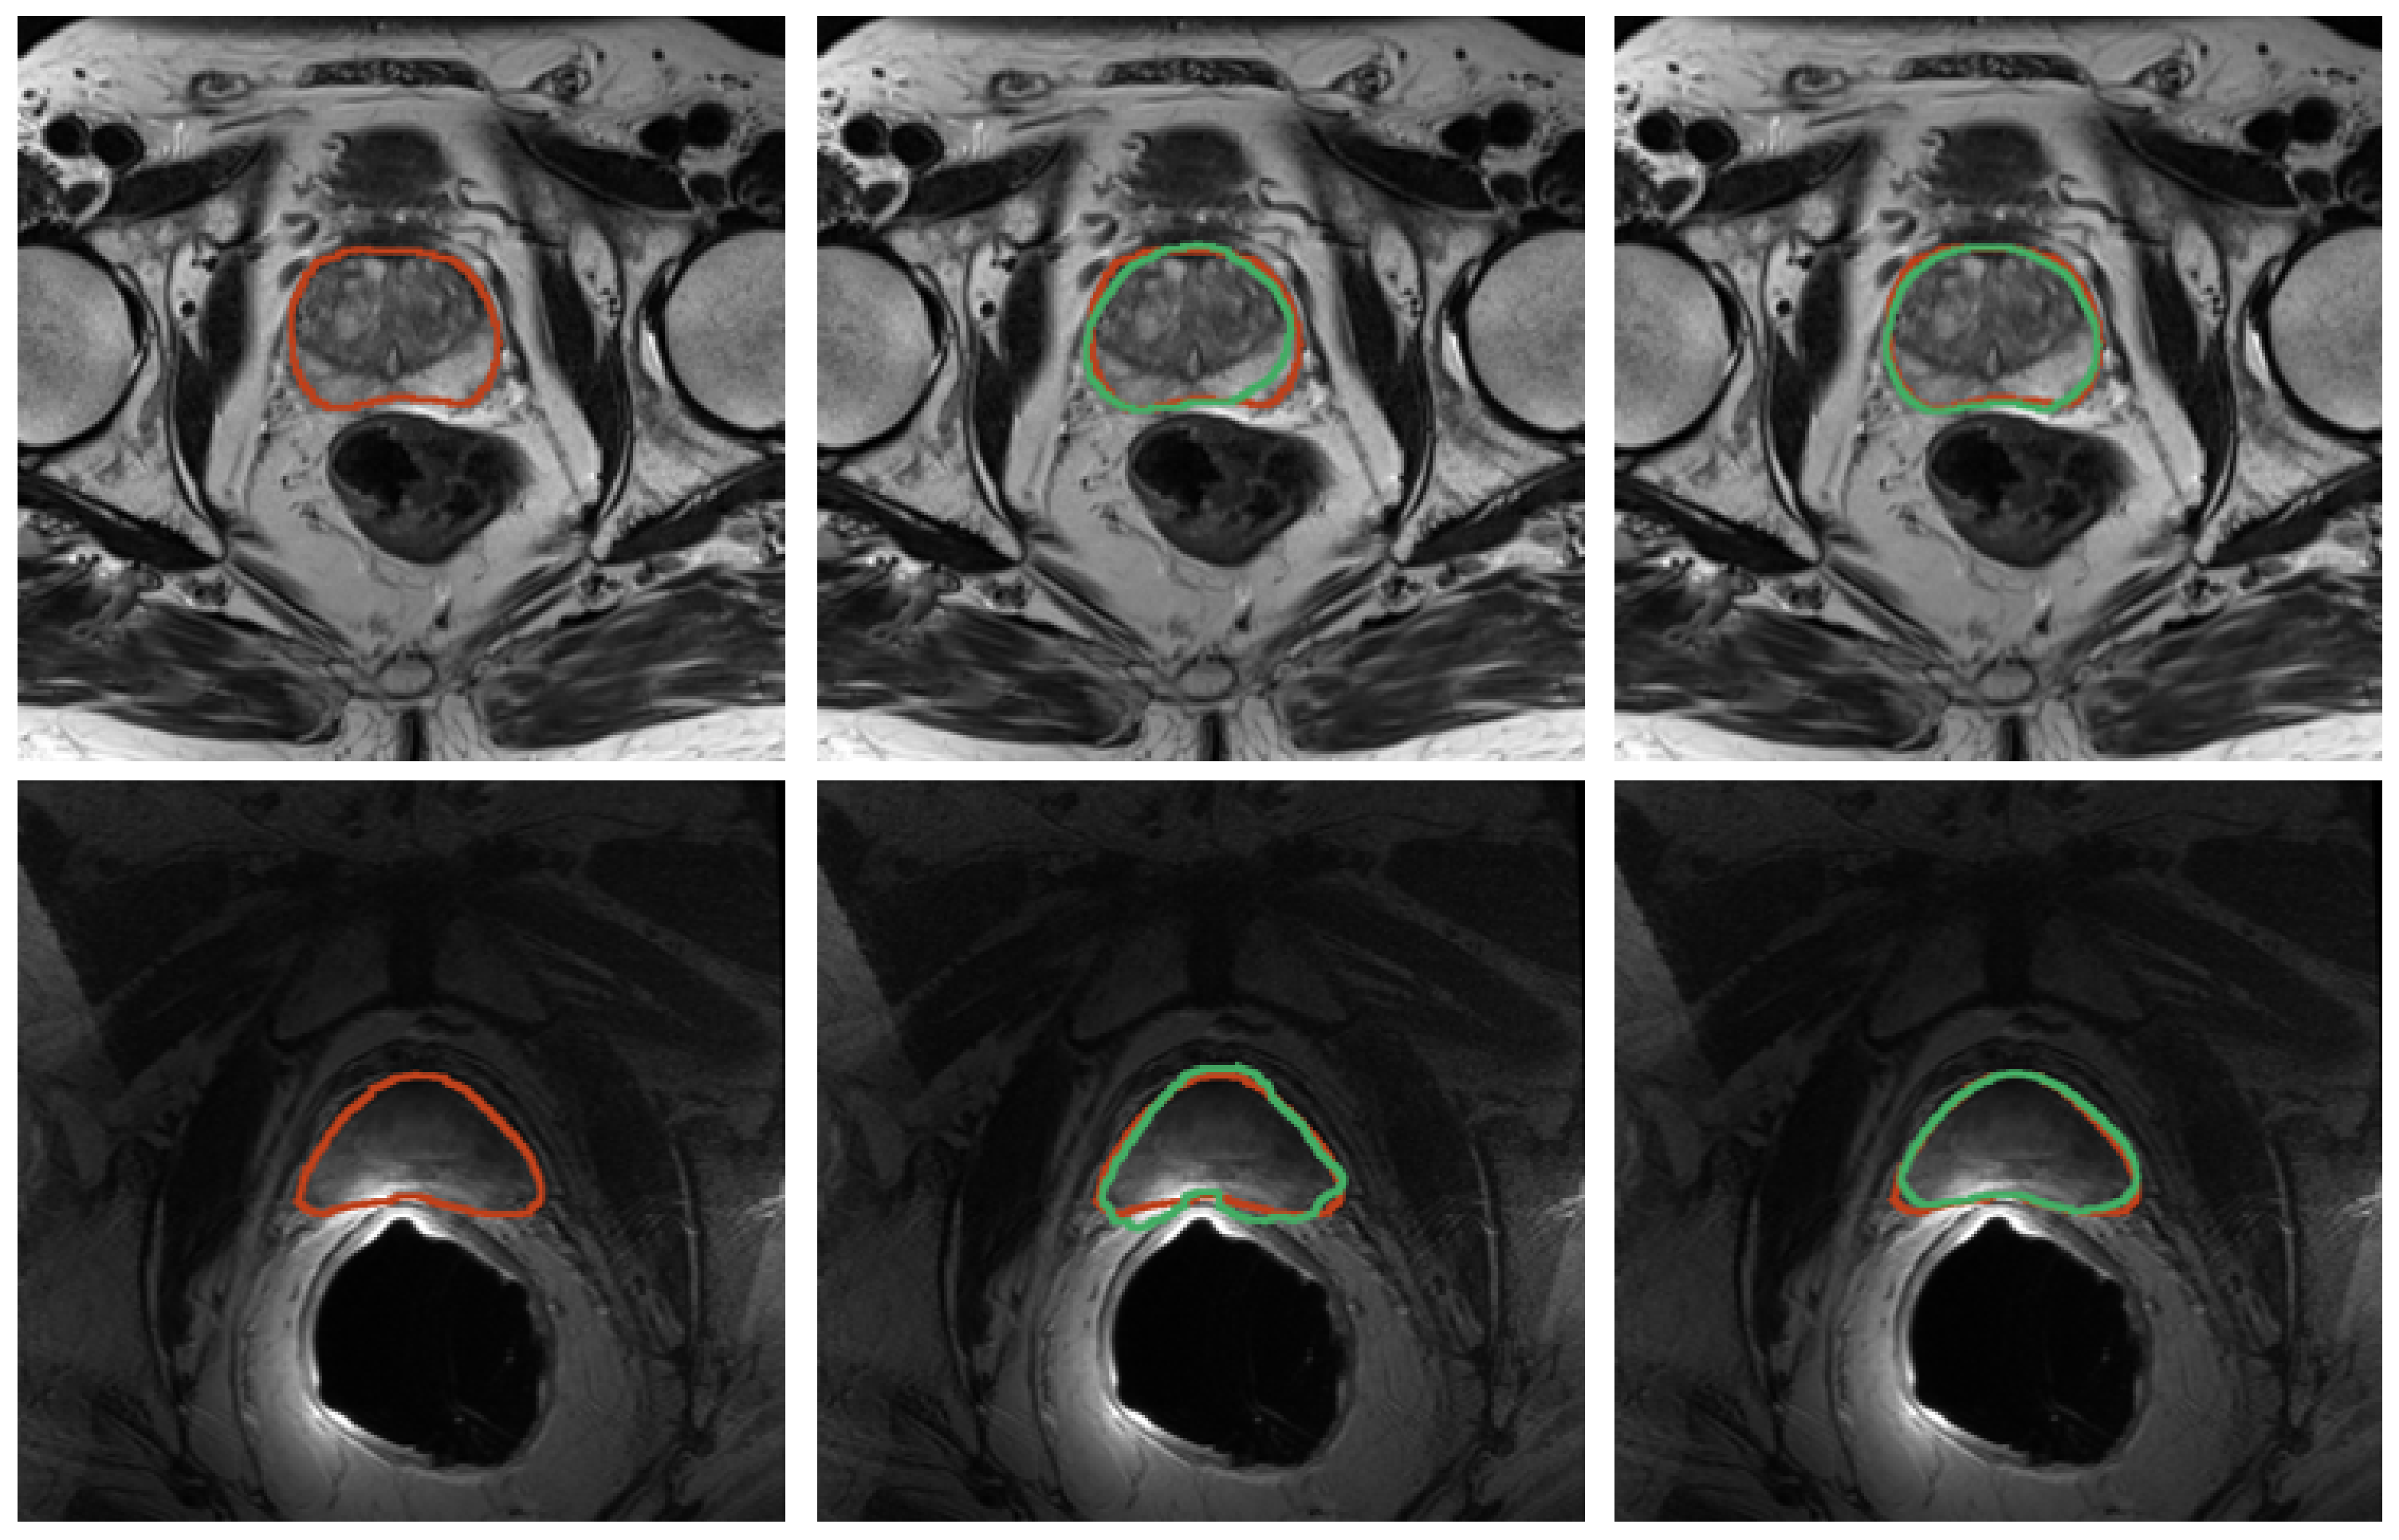

Figure 8.

Results for prostate segmentation from MRI. Top row contains images from the SAML dataset and the second row contains images from ZENODO. The ground truth is represented in red, whereas the predictions from the nnU-Net models are colored in green. The middle image shows the prediction mask for the nnU-Net trained for only 10 epochs, whereas the right image depicts the prediction mask for the one trained on the PROMISE12 dataset.